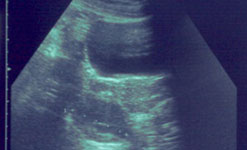

An ultrasound scan showing

PCOS cysts on an ovary |

Polycystic Ovary Syndrome In this week’s Check Up, Barbara Myers and her guest Professor Adam Balen from Leeds General Infirmary will be offering advice about Polycystic Ovary Syndrome.

Weight gain, excessive body hair, acne and irregular periods are just some of a myriad of symptoms that women with polycystic ovary syndrome (PCOS) can suffer from.